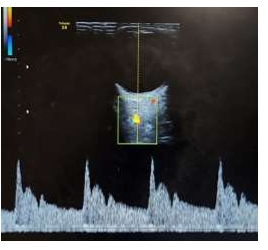

Assinale a alternativa CORRETA que representa a imagem de maior risco para pré-eclâmpsia, considerando as

pacientes com mesmo quadro clínico e obstétrico.